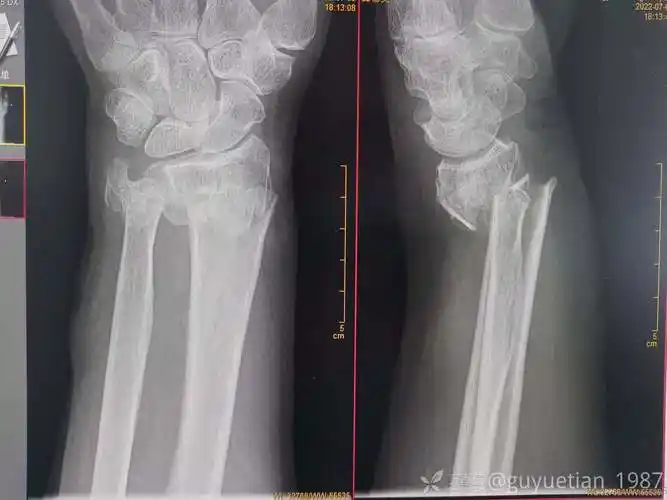

一例桡骨远端骨折复位 [病例帖]

手法整复,夹板外固定治疗成人桡骨远端骨折

桡骨远端骨折手法复位

男孩,9岁,左桡骨远端骨折

桡骨远端骨折保守